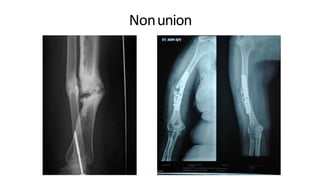

Nonunion

DPS